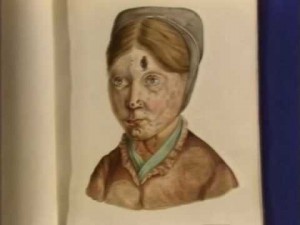

One of Losting’s famous portraits of a woman with leprosy in St Jørgen’s Hospital, Bergen, Norway

You Tube: On Leprosy (based on Danielssen and Boëck’s Atlas)